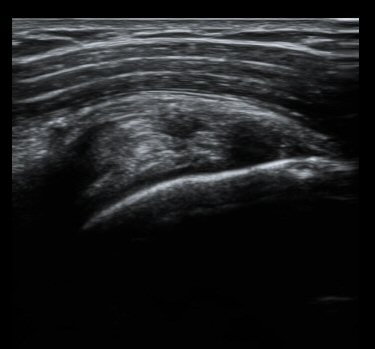

ȸÀü±Ù°³°£°Ý Ⱦ´Ü¸é°Ë»ç¿¡¼­ Á¡¾×³¶³» ¼ö¾×Àú·ù°¡ °üÂûµÈ´Ù(±×¸² 1). ÀÌµÎ¹Ú±Ù°Ç °í¶û¿¡¼­´Â ƯÀÌ ¼Ò°ßÀ» º¸ÀÌÁö ¾Ê´Â´Ù(±×¸² 2). ȸÀü±Ù°³°£°Ý ³»Ãø¿¡¼­ °ß°©ÇϱٰÇÀÇ ÆÄ¿­°ú Á¡¾×³¶³» ¼ö¾×Àú·ù°¡ °üÂûµÈ´Ù(±×¸² 3, 4). ±Ø»ó°Ç Ⱦ´Ü